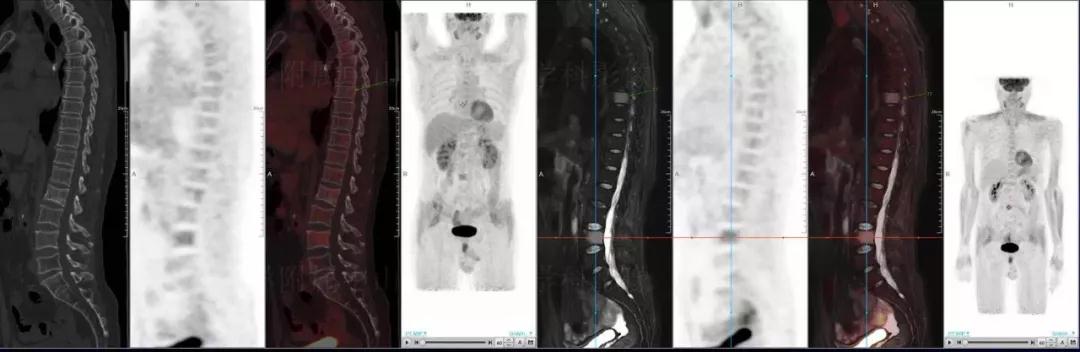

多發(fā)性骨髓瘤

中山醫(yī)院核醫(yī)學科基于聯(lián)影“時空一體”超清TOF PET/MR的融合顯像優(yōu)勢,進行了大量的臨床掃描,發(fā)現(xiàn)多例由MGUS向多發(fā)性骨髓瘤轉變,并從中總結出了一定的共同征象,未來可能實現(xiàn)多發(fā)性骨髓瘤的早期篩查。此外,PET/MR在多發(fā)性骨髓瘤的療效評估方面,也存在顯著優(yōu)勢。

(男性,53歲。確診多發(fā)性骨髓瘤10月。經(jīng)過7周期VCD方案化療后,現(xiàn)行療效評價。)